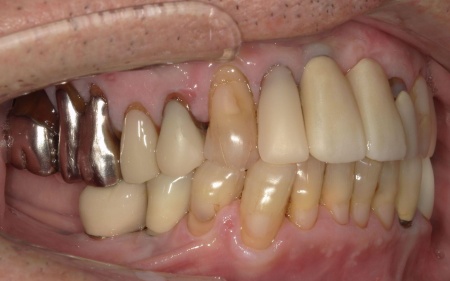

70代男性 右下奥歯を抜いてインプラント治療で噛み合わせを回復した症例

拝見したところ、右下奥歯(第2小臼歯)の周辺組織に炎症が広がり、歯茎が赤く腫れていました。

まずは投薬治療を行いましたが、症状の改善は見られませんでした。

患者様には「投薬で効果が見られない場合は抜歯が必要になる可能性がある」とお伝えしていたため、抜歯後にインプラント治療を行う提案をし、同意いただきました。

まず、右下奥歯(第2小臼歯)を抜き、骨が治癒するのを待ってから、インプラントを埋入します。

インプラントと顎の骨がしっかりと結合したら、精密な型取りを行い、インプラント上部に装着する最終的な被せ物を作製しました。

最後に完成した被せ物を装着し、見た目や噛み合わせに問題がないことを確認して、治療を終了しています。